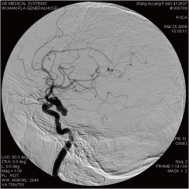

右侧颈内动脉后交通动脉瘤栓塞术前 左椎动脉造影 示左椎动脉夹层动脉瘤: 左椎动脉发出小脑后下动脉处呈囊性扩张,动脉瘤远端血管狭窄

颈内动脉创伤性假性动脉瘤覆膜支架治疗前后(三维像是术前) 右侧颈内动脉后交通动脉瘤栓塞术后完全闭塞

弹簧圈栓塞后造影示左椎动脉夹层动脉瘤消失, 左椎动脉、 多发动脉瘤夹闭术前、术中

左侧小脑后下动脉循环通畅